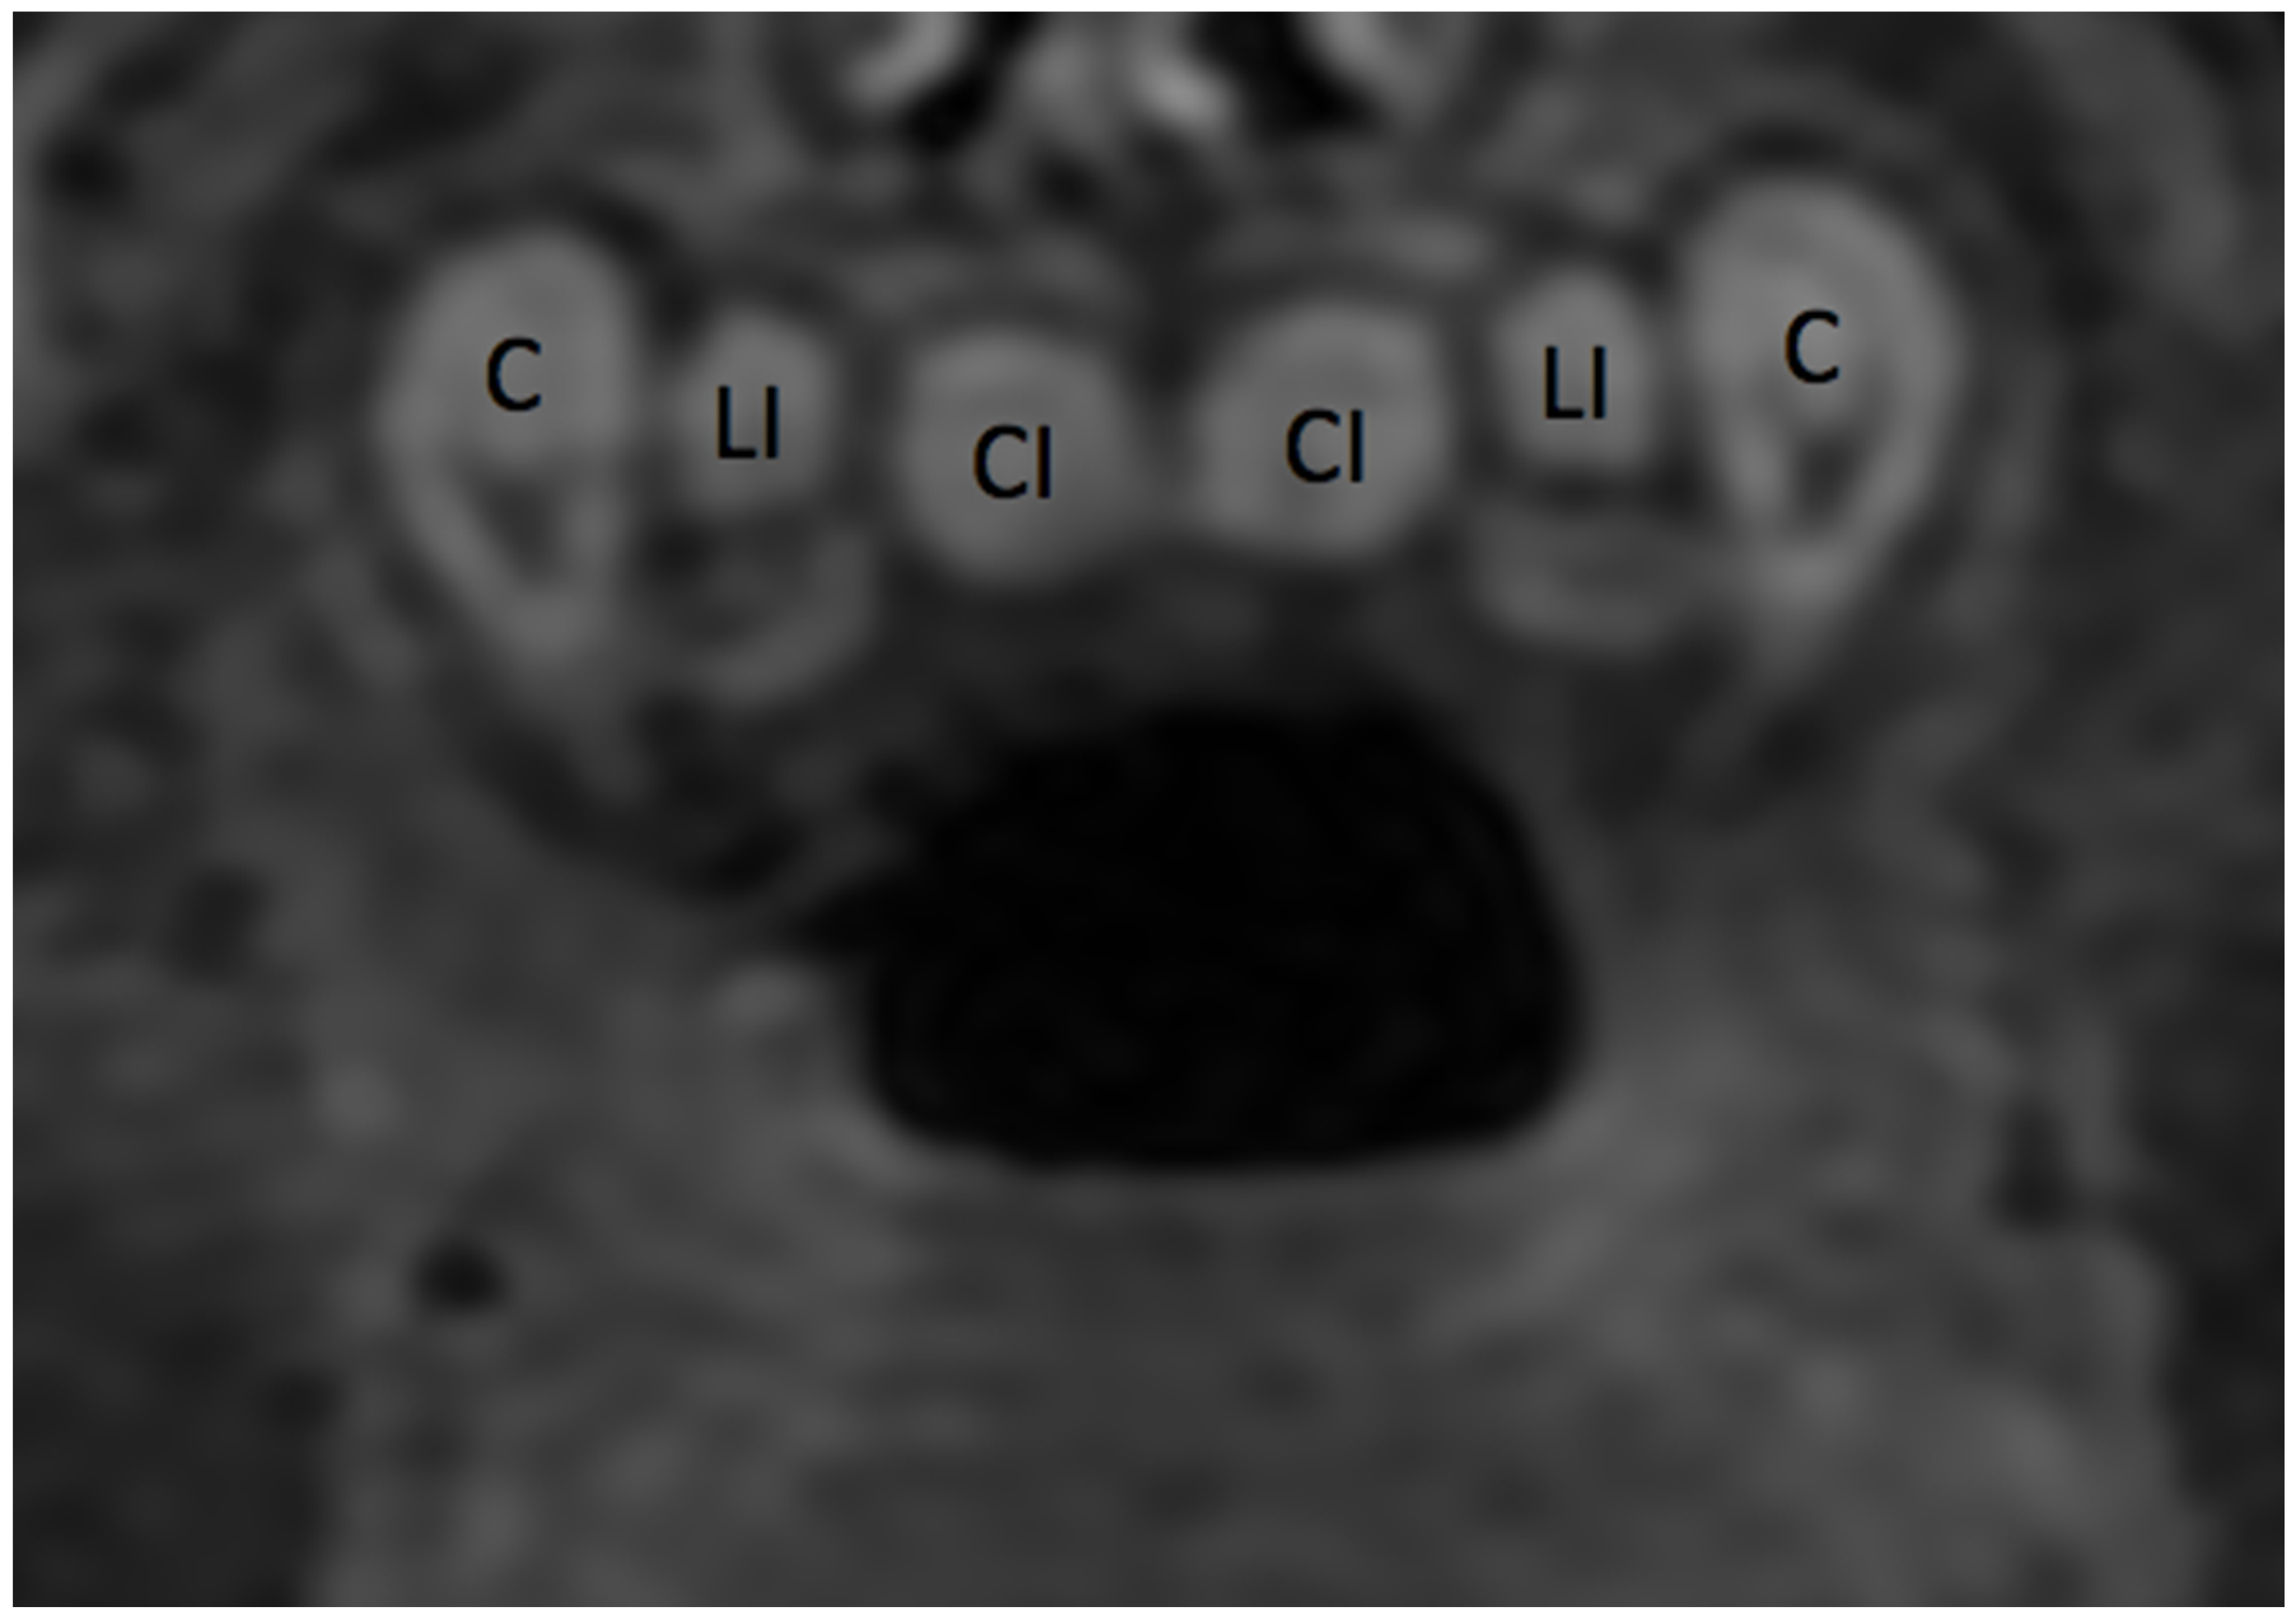

3.1. Anatomy of the Dental Arch

3.1.1. Anatomy of Tooth Structure